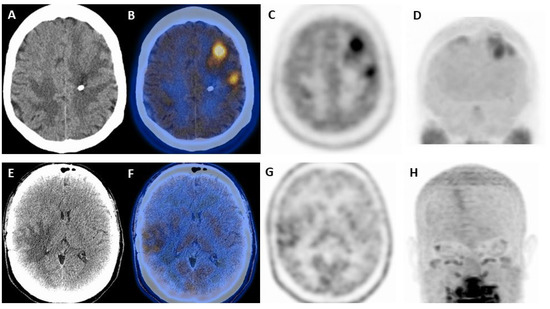

| Horky et al. [27] | 2011 | R | Solid neoplasms | 32 (10/22) | Dual phase PET/CT to differentiate recurrence from radionecrosis | Variation of L/GM > 0.19 between early and delayed: Sensitivity 955% Specificity 100% Accuracy 96% |

| Hatzoglou et al. [28] | 2016 | P | BM, gliomas | 53 (35/18) | To differentiate between recurrence and radionecrosis using PET/CT and DCE MRI | Vp ratio = 2.1 showed highest accuracy: Sensitivity 92% Specificity 77% |

| Leiva-Salinas et al. [29] | 2019 | R | BM | 85 (37/48) | To determinate if PET/MRI predicts recurrence after radiosurgery | Relative SUV = 1.75: Sensitivity 87% Specificity 32% |